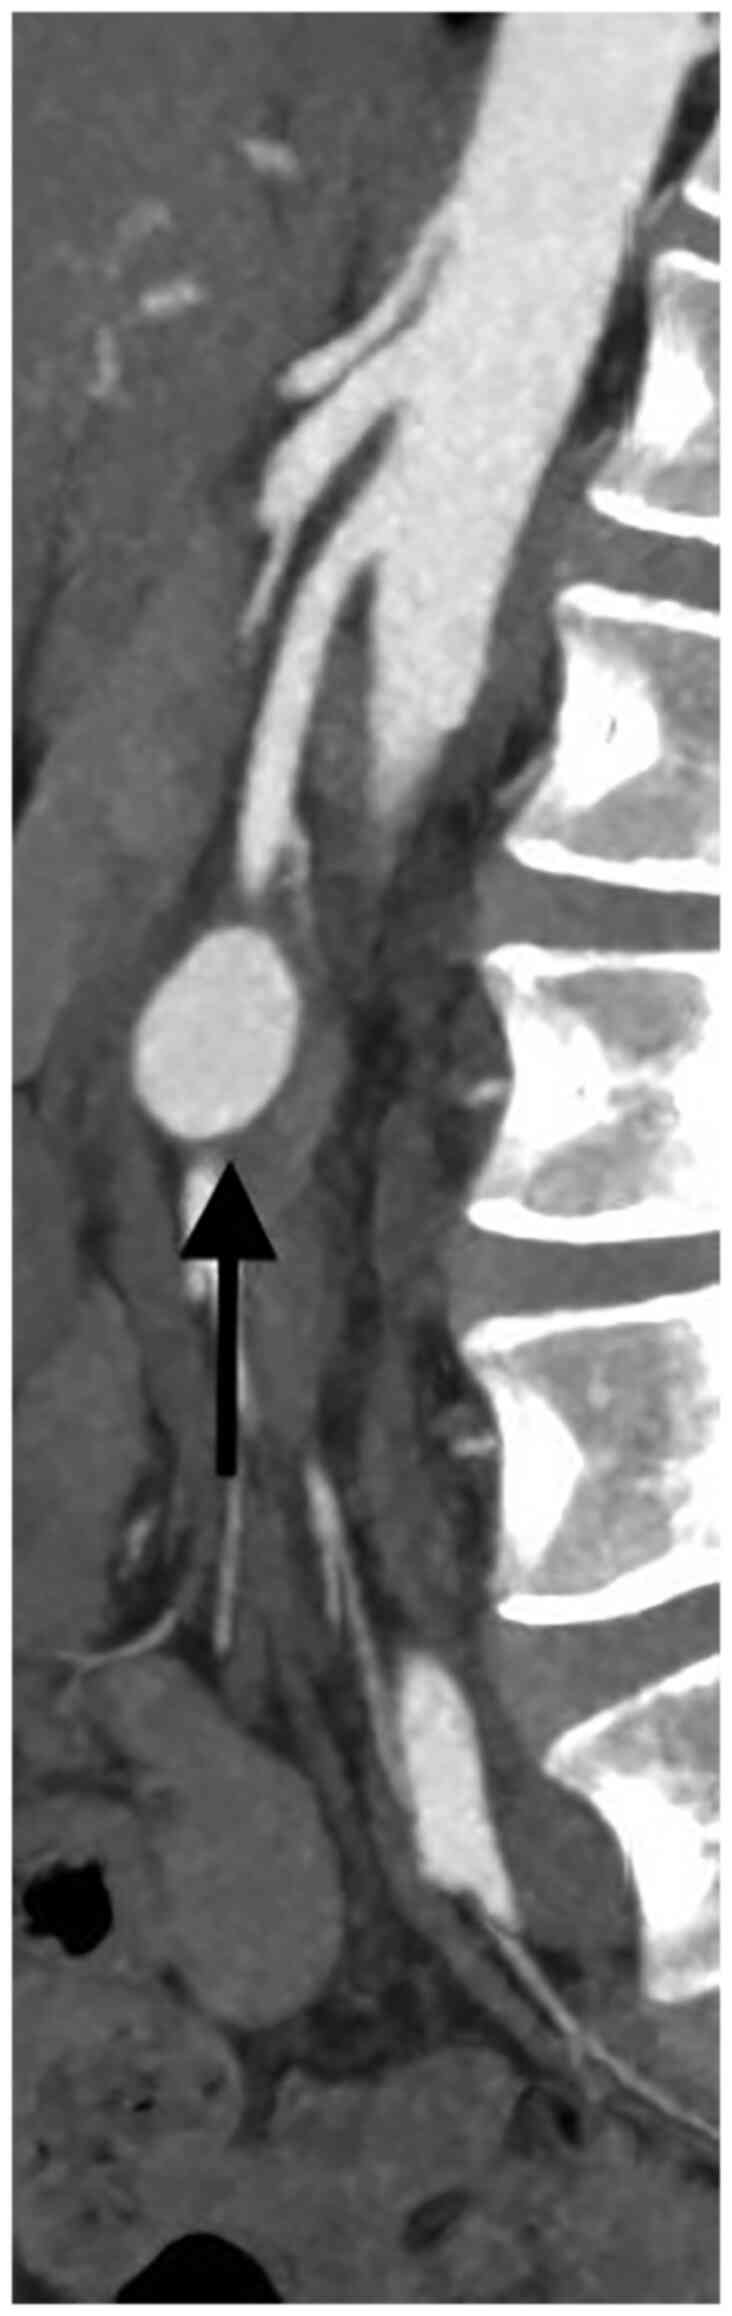

Visceral artery aneurysms are defined in this retrospective analysis as a true aneurysm in the celiac trunk (CT), superior mesenteric artery (SMA), inferior mesenteric artery, and/or their branches. Visceral artery aneurysms (VAAs) are rare and mostly asymptomatic., Rapid growth, size >2 cm, and pregnancy are risk factors associated with rupture. True visceral aneurysms are aneurysms are the result of weakening and thinning of the artery wall. Atherosclerosis, connective tissue disorders, infection (for example pancreatitis) and abdominal surgery are known risk factors for the development of VAA. Nowadays, conservative therapy, endovascular, and open surgery are the treatment options for patients with visceral aneurysms (VAA). During the last decade, endovascular repair of VAAs has been increasingly used (1-6). Catheter-based embolization or stent-graft placement are two major treatment options. Most VAAs originate from the splenic artery (SA) (60%) (Figs. 1 and 2), followed by the hepatic artery (HA) (20-50%) (Figs. 3 and 4). An origin from the superior mesenteric artery (SMA) (6%) (Figs. 5 and 6), the celiac trunk (CT) (4%) or other, smaller visceral arteries is considerably less common (7).

There were eight patients with an aneurysm of the SA, two patients with aneurysms of the SMA, one patient with an aneurysm of the HA and one patient with an aneurysm of the CT. Only one patient was symptomatic and presented with signs of bleeding. All patients received a contrast-enhanced CT-scan.

The median aneurysm diameter was 2 cm (range 1.5 cm to 5 cm) for all aneurysms, 3.75 cm for aneurysms of the SMA, 2 cm for aneurysms of the SA and for aneurysms of the CT and 1.5 for the aneurysm of the HA.